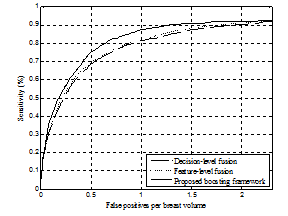

그림 3. 기존 정보 융합 분류 방법들과 제안 방법의 FROC 분류 성능 비교. 제안 방법이 기존 정보 융합 방법(decision-level fusion, feature-level fusion)보다 두 영상에서 추출된 다양한 특징 정보를 효과적으로 융합함을 보임.

In digital breast tomosynthesis (DBT), image characteristics of projection views and reconstructed volume are different and both have the advantage of detecting breast masses, e.g. reconstructed volume mitigates a tissue overlap, while projection views have less reconstruction blur artifacts. In this paper, an improved mass detection is proposed by using combined feature representations from projection views and reconstructed volume in the DBT. To take advantage of complementary effects on different image characteristics of both data, combined feature representations are extracted from both projection views and reconstructed volume concurrently. An indirect region-of-interest segmentation in projection views, which projects volume-of-interest in reconstructed volume into the corresponding projection views, is proposed to extract combined feature representations. In addition, a boosting based classification with feature selection has been employed for selecting effective feature representations among a large number of combined feature representations, and for reducing false positives. Experiments have been conducted on a clinical data set that contains malignant masses. Experimental results demonstrate that the proposed mass detection can achieve high sensitivity with a small number of false positives. In addition, the experimental results demonstrate that the selected feature representations for classifying masses complementarily come from both projection views and reconstructed volume.Author information

- 최근 digital breast tomosynthesis (DBT)가 새로운 유방 영상 촬영술로 주목을 받고 있습니다. DBT의 2차원 투영영상(projection views)과 3차원 단면영상(reconstructed volume)은 상보적 영상 특성을 가지고 있어, 병변(mass) 자동 검출에 두 영상 정보를 모두 분석하는 것이 효과적 입니다. 이를 위해 본 논문은 두 영상에서 병변의 융합 특징 정보를 추출하고, boosting 및 다중 분류기 기반 병변 특징 선택/분류 방법을 제안하였습니다. 실험을 통해 두 영상 정보를 모두 분석 시 병변 분류 성능이 향상됨을 보였고 (그림 1), 분류에 중요한 병변 정보를 포함하여 자주 선택된 특징 정보들이 두 영상에 모두 분포하여 상보적임을 보였습니다 (그림 2). 또한 기존 정보 융합 방법 대비 우수한 분류 성능을 보여 (그림 3) DBT 투영영상과 단면영상 특징 융합 분석, 위양성 감소 (그림 4)에 효과적임을 보였습니다. 본 연구는 다중 영상 융합 분석, DBT 영상 특징 분석에 관심 있는 연구자들에게 도움이 될 좋은 정보라 생각합니다.